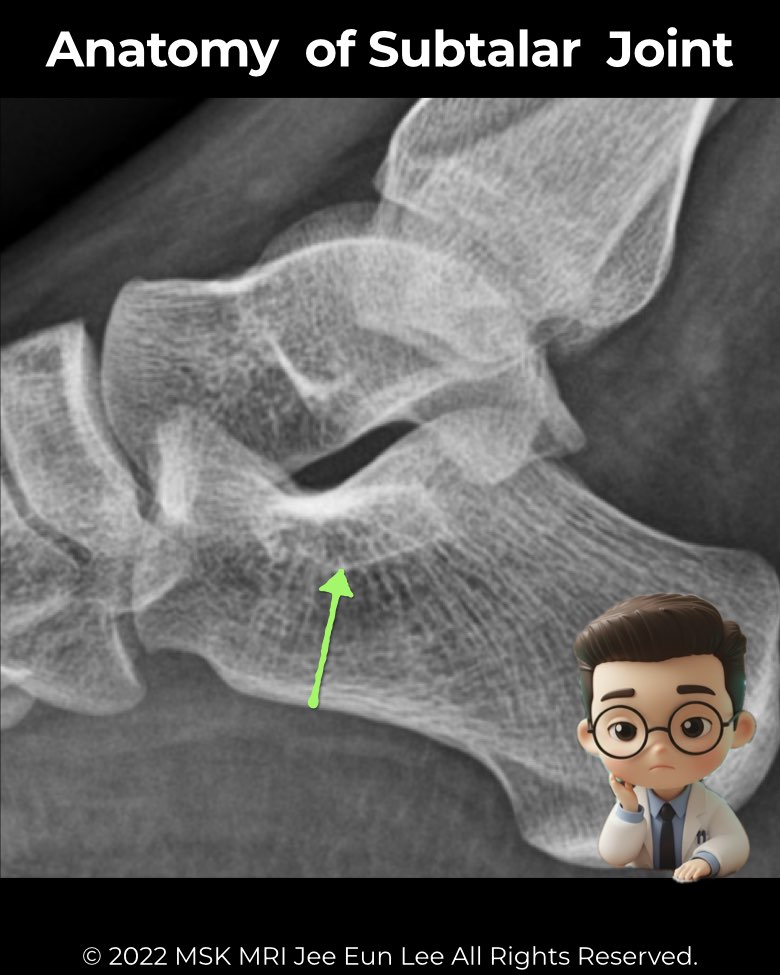

The subtalar joint (talocalcaneal joint) is vital for hindfoot stability and mobility.

- Posterior facet: largest, best seen on lateral radiographs and CT

- Middle facet: on the sustentaculum tali, may communicate with the talonavicular joint

- Anterior facet: smallest, may merge with the middle facet

- Sustentaculum tali appears brick-shaped on lateral X-ray

- Anterior calcaneal process should not articulate with the navicular—if it does, think coalition